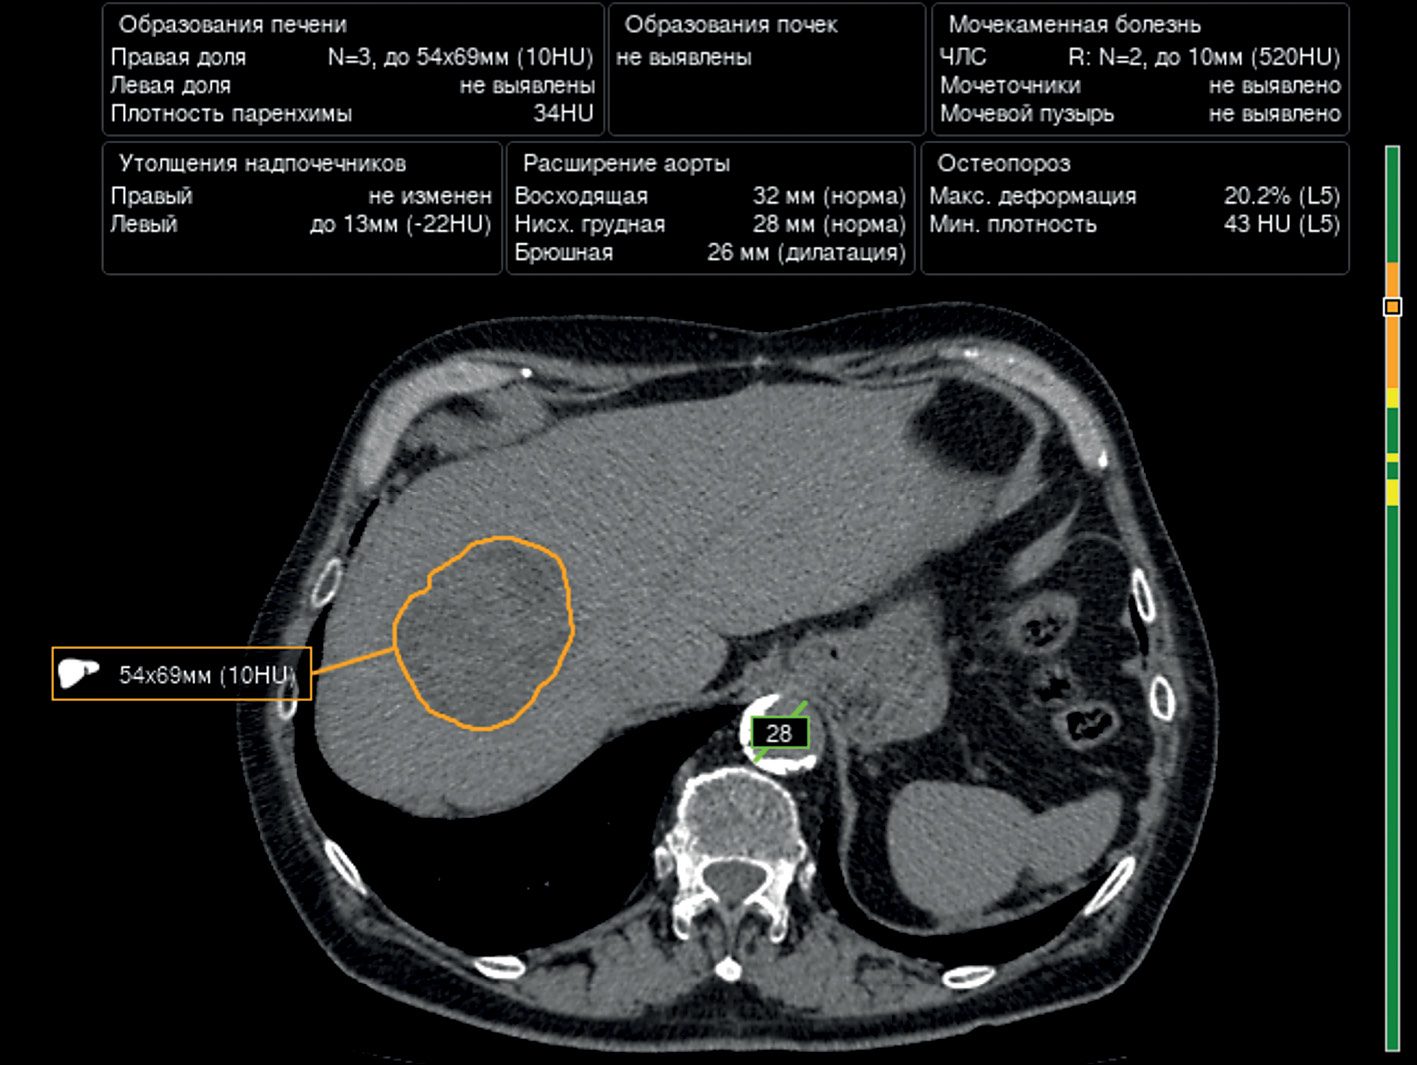

Prospects of using computer vision technology to detect urinary stones and liver and kidney neoplasms on computed tomography images of the abdomen and retroperitoneal space

The article presents a selective literature review on the use of computer vision algorithms for the diagnosis of liver and kidney neoplasms and urinary stones using computed tomography images of the abdomen and retroperitoneal space. The review included articles published between January 1, 2020, and April 24, 2023. Pixel-based algorithms showed the greatest diagnostic accuracy parameters for segmenting the liver and its neoplasms (accuracy, 99.6%; Dice similarity coefficient, 0.99). Voxel-based algorithms were superior at classifying liver neoplasms (accuracy, 82.5%). Pixel- and voxel-based algorithms fared equally well in segmenting kidneys and their neoplasms, as well as classifying kidney tumors (accuracy, 99.3%; Dice similarity coefficient, 0.97). Computer vision algorithms can detect urinary stones measuring 3 mm or larger with a high degree of accuracy of up to 93.0%. Thus, existing computer vision algorithms not only effectively detect liver and kidney neoplasms and urinary stones but also accurately determine their quantitative and qualitative characteristics. Evaluating voxel data improves the accuracy of neoplasm type determination since the algorithm analyzes the neoplasm in three dimensions rather than only the plane of one slice.